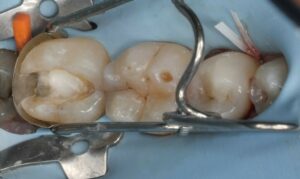

Abbildung 4: Präzise Platzierung von GrandioSO Heavy Flow (Farbe WO) zur Versiegelung von MTA vpt unmittelbar nach der Applikation.